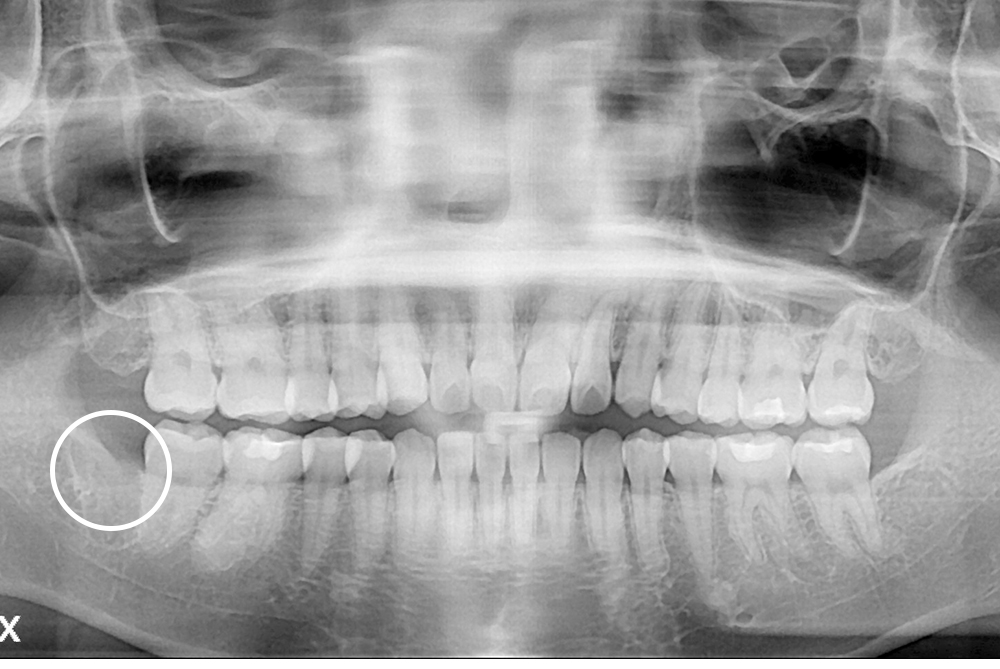

[사랑니] 매복 사랑니 발치

치료전 : 2016-03-18